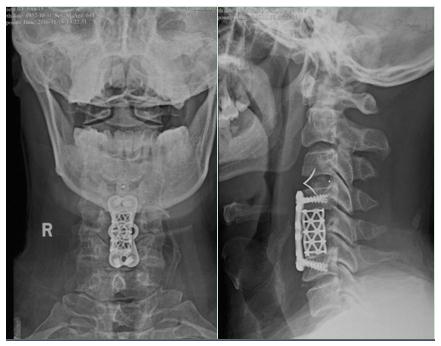

患者颈椎CT显示“颈椎管狭窄”;颈椎MRI显示颈3/4、颈4/5、颈5/6椎间盘向后巨大突出,尤其是颈4/5的椎间盘髓核组织突出并向下掉落到颈5椎体后缘,将脊髓压的只剩一条细线,脊髓水肿严重(见下图),增加了颈椎手术难度和风险。

这种手术的设计理论说起来简单,但实际操作并非易事,需要医生巧妙把握手术入路及切除的椎体部位。杜俊杰轻巧准确地在患者颈前横向切开一个约5cm的切口,在这么小的切口下完成3个节段的减压,需要很高的手术技巧。手术中,他凭借扎实的临床手术功底,避开患者颈椎前方重要血管、神经、食管、气管、甲状腺等众多组织结构,准确找到病患位置,在助手的配合下,一气呵成切除了患者颈椎管狭窄伴3个节段椎间盘巨大突出,为患者彻底清除了脊髓前方的压迫(见下图)。不仅解除了患者脊髓压迫症状,还恢复了其颈椎正常的生理前曲。手术历时约2小时,出血仅10毫升。